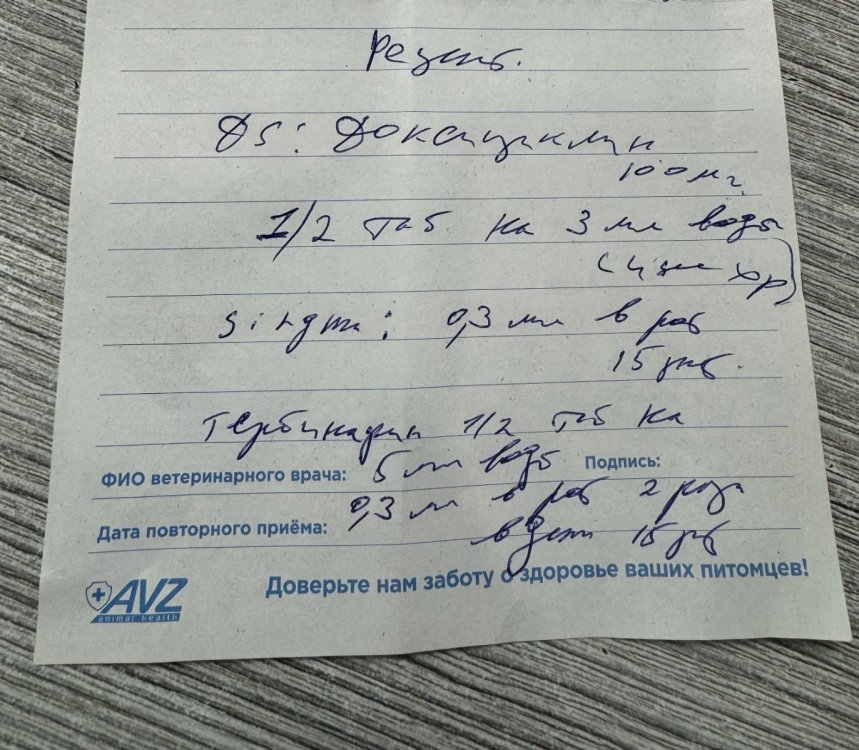

расскажите пожалуйста про дозировки а срок 15 дней недостаточен поскольку у нас нет анализа с результатом "микоплазмоз - отрицательно" поскольку голубь кормил малыша из клюва то да нужно как сейчас весит и выглядит малыш? рахита у него не было? при лечении доксициклином малыши плохо растут так как доксициклин НЕ совместим с кальцием очень неплохо! вес дикого сизарика обычно 250-300 грамм (320 грамм бывают хорошо откормленные крупные самцы) потому при таком весе доксицклин на росте не скажется скорее всего он проглотит но может и откашлянуть и выплюнуть отвар крапивы или подорожника нужен заранее улучшить сворачиваемость крови чтобы нарост по возможности отвалился бескровно если нарост на кости или на корне языка бывает что отваливается вместе с челюстью или с языком потому заранее проверить (в этом случае подключают антибиотик от некроза) ещё бывает ужас когда нарост на пищеводе вдоль шеи а вот на зобу выглядит страшно гораздо безопаснее и хорошо заживает тема про трихомоноз https://www.mybirds.ru/forums/topic/65174-trihomonoz/